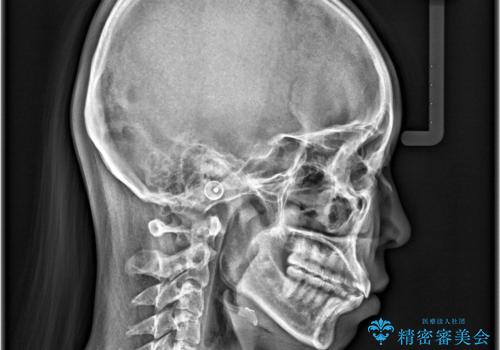

【インビザライン】前歯が出ているのを治したい

- 前歯が出ていることを主訴に来院されました。

前歯の突出感が改善され、満足していただきました。